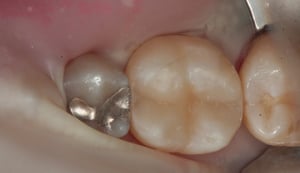

Otturazione in composito a livello di primo molare inferiore destro. Il restauro in amalgama di argento esistente presenta una frattura e viene pertanto sostituito. La rimozione del materiale metallico viene eseguita isolando il dente dal cavo orale mediante diga di gomma. Il dente viene come per ogni procedura sabbiato, mordenzato, trattato con primer ed adesivi ed infine otturato in materiale composito fotopolimerizzabile. La presenza di cuspidi intatte e di spessore sufficiente, conferisce una adeguata resistenza meccanica al restauro eseguito.